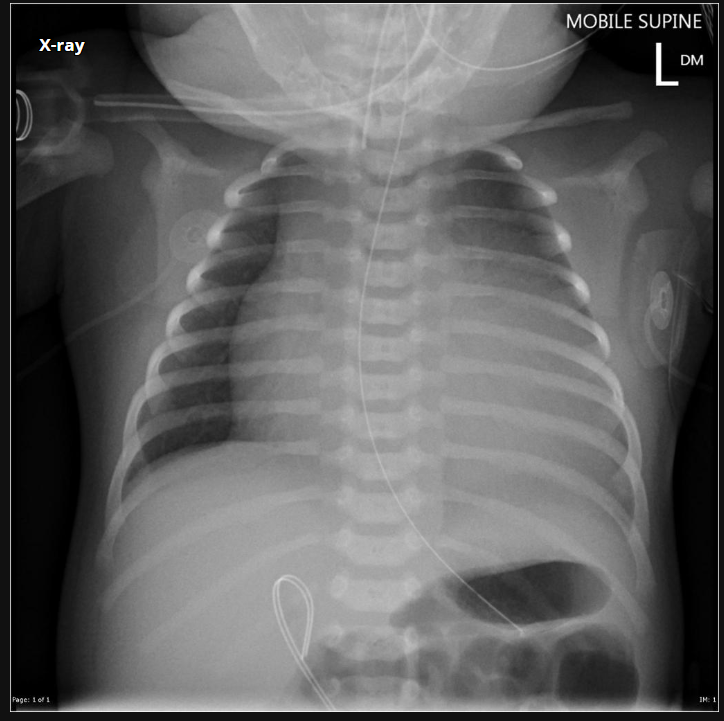

RN a termo.

Cardiomegalia massiva em um neonato com pulmão normal (sem edema alveolar ou intersticial, sem derrame pleural)

Cardiomiopatia neonatal.